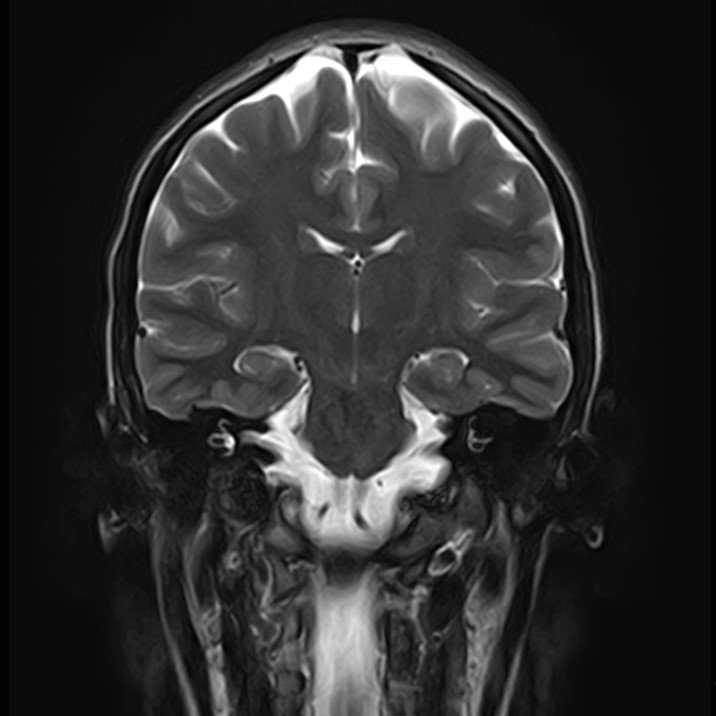

3. При головной боли, надо обязательно сделать МРТ

Действительно, зачастую приходят на МРТ пациенты, страдающие головной болью. Однако, в подавляющих случаях, МРТ не дает каких-то неблагоприятных результатов. Такая головная боль, как правило, связана с психоэмоциональными или психофизиологическими особенностями как организма, так и образа жизни (стресс, переутомление, несоблюдение режима труда и отдыха и т.д.). Но стоит отметить, что проведение МРТ даст дополнительную информацию Вам о состояние головного мозга и тем самым “успокоит” Вас.